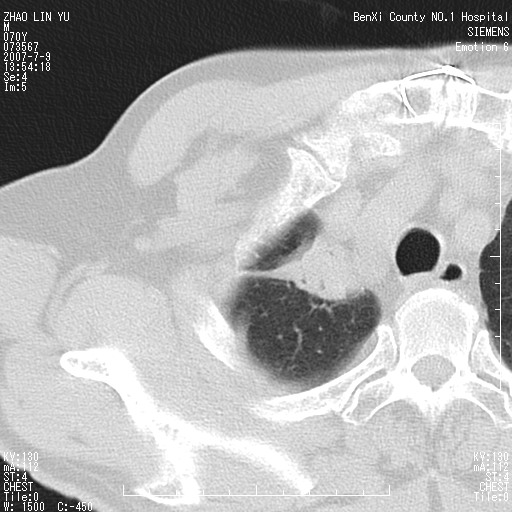

以下是引用王靖旗在2007-7-10 17:12:00的发言:[br] 男、70、咳嗽两个月,半年前换瓣手术,胸片未见异常,于昨天行x片发现右肺上野大片影,行ct扫描,这里是减薄图像,余肺正常。明天晚上会有增强扫描片,到时我会上传。[br][br] 冠状位请大家细看,应该是有意义的,[br][br] 请大家先看平扫发表意见。[br][br]

以下是引用zhangzhongshou在2007-7-10 21:43:00的发言:[br]右肺上叶周围型肺癌,以孤立型细支气管肺泡癌可能性大。